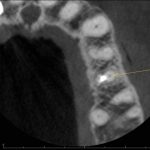

Cone Beam Case Study:  Abscess on #24

Cone Beam Case Study:  Obturation of #13